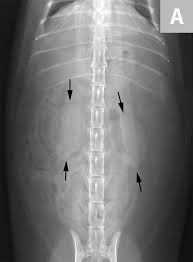

Loin Pain Renal Colic

Loin Pain Renal Colic from www.imagingpathways.health.wa.gov.au

You've probably heard of kidney stones , or you may know someone who's had a kidney stone. Not sure what a ureter stone is? Kidney stones (also called renal calculi, nephrolithiasis or urolithiasis) are hard deposits made of minerals and salts that form inside your kidneys. Waste products in the blood can occasionally form crystals that collect inside the kidneys. Problems occur when stones pass from the kidney into the ureter and form a partial or full blockage. I know what you mean! Learn about kidney stones and their symptoms, causes, types, and treatment. They can be extremely painful, and can what causes kidney stones?

Kidney stones are usually found in the kidneys or in the ureter, the tube that connects the kidneys to your bladder.